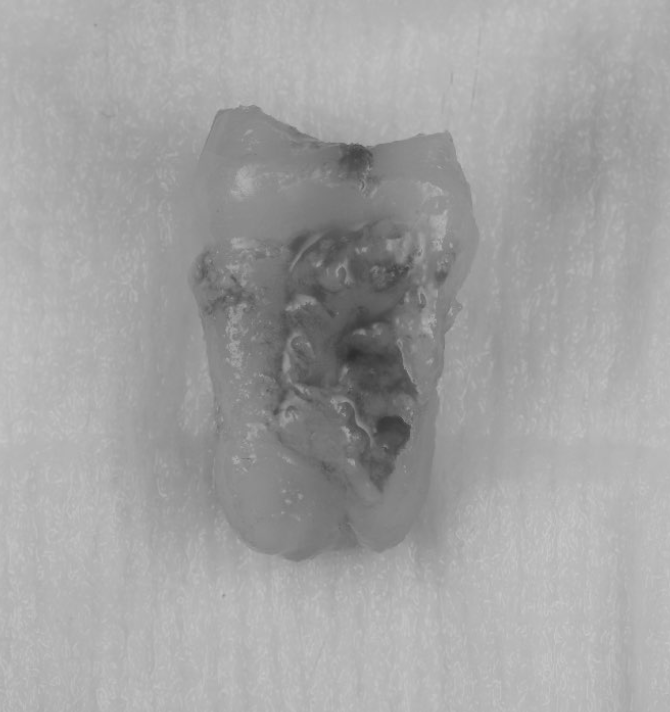

【池袋 歯医者】歯根嚢胞に対する歯根端切除術とは...